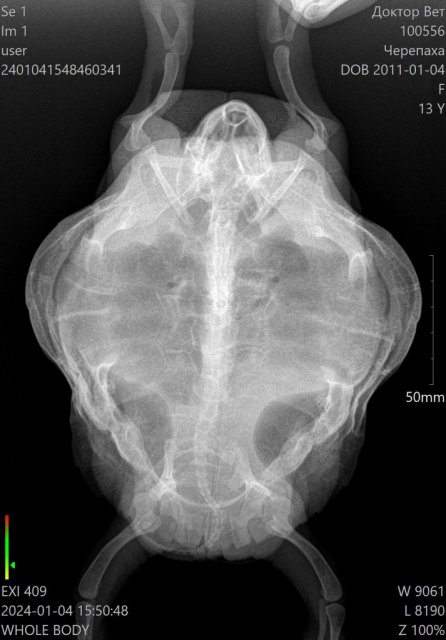

Lara6 Ваше имя: Лариса Локация: Якутск Опубликовано: 4 января 2024 Автор Опубликовано: 4 января 2024 @moth @moth сходили на снимок

Консультанты moth Ваше имя: Мария Локация: Москва Опубликовано: 5 января 2024 Консультанты Опубликовано: 5 января 2024 @Lara6 врачу нашему скинула, но у меня к назначениям вопросы кололи в переднюю лапу? пневмонию поставили по вот этому рентгену что был? если да, то это не герпетолог. По этой проекции лёгкие вообще не видно.